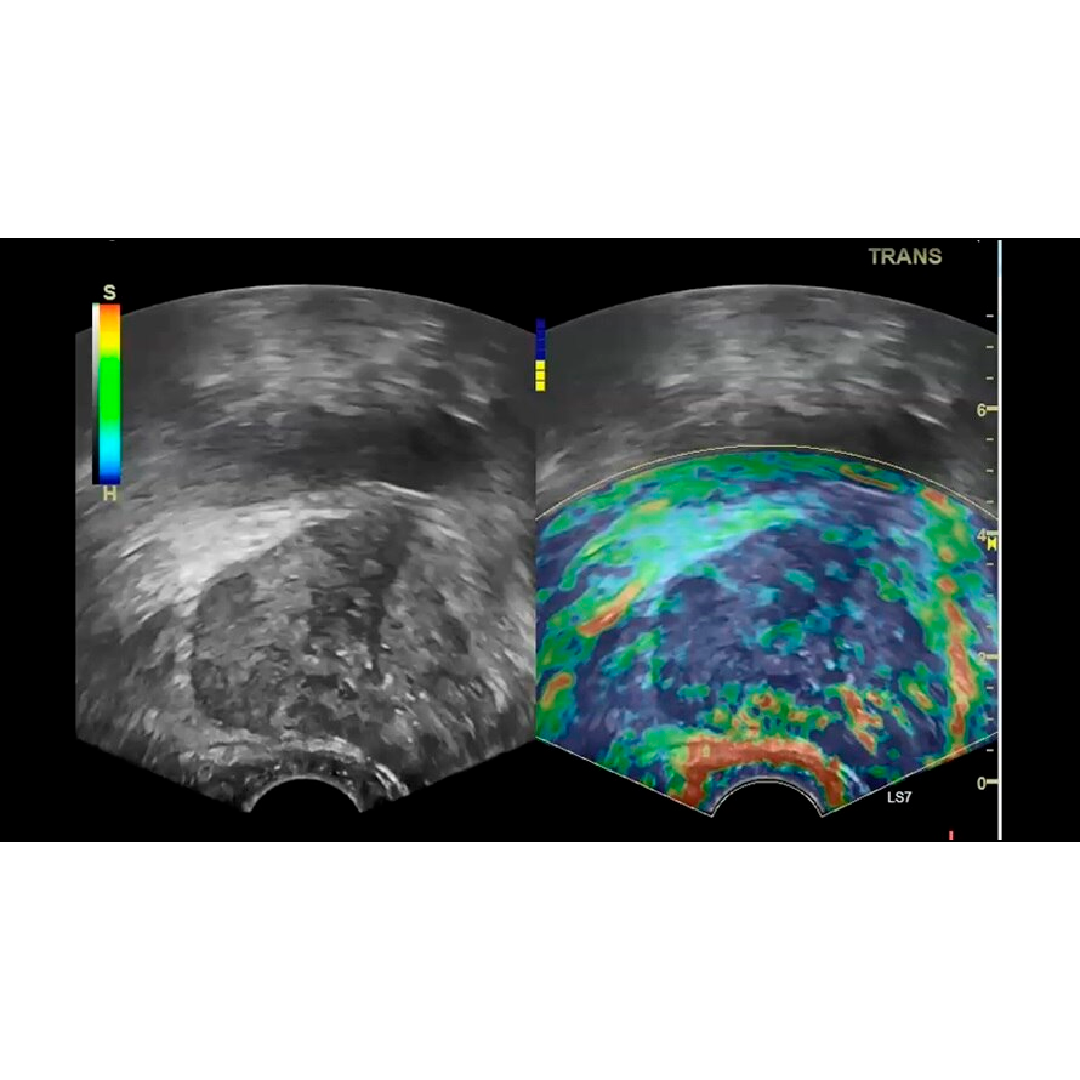

Elastografía por ondas de corte en 2D

Proporciona una evaluación cuantitativa y no invasiva de la rigidez tisular y se puede utilizar con la navegación volumétrica.

Imágenes clínicas

El equilibrio entre rendimiento y precio en un examen ligero y portátil. Vea y cuantifique la enfermedad hepática en un solo examen.